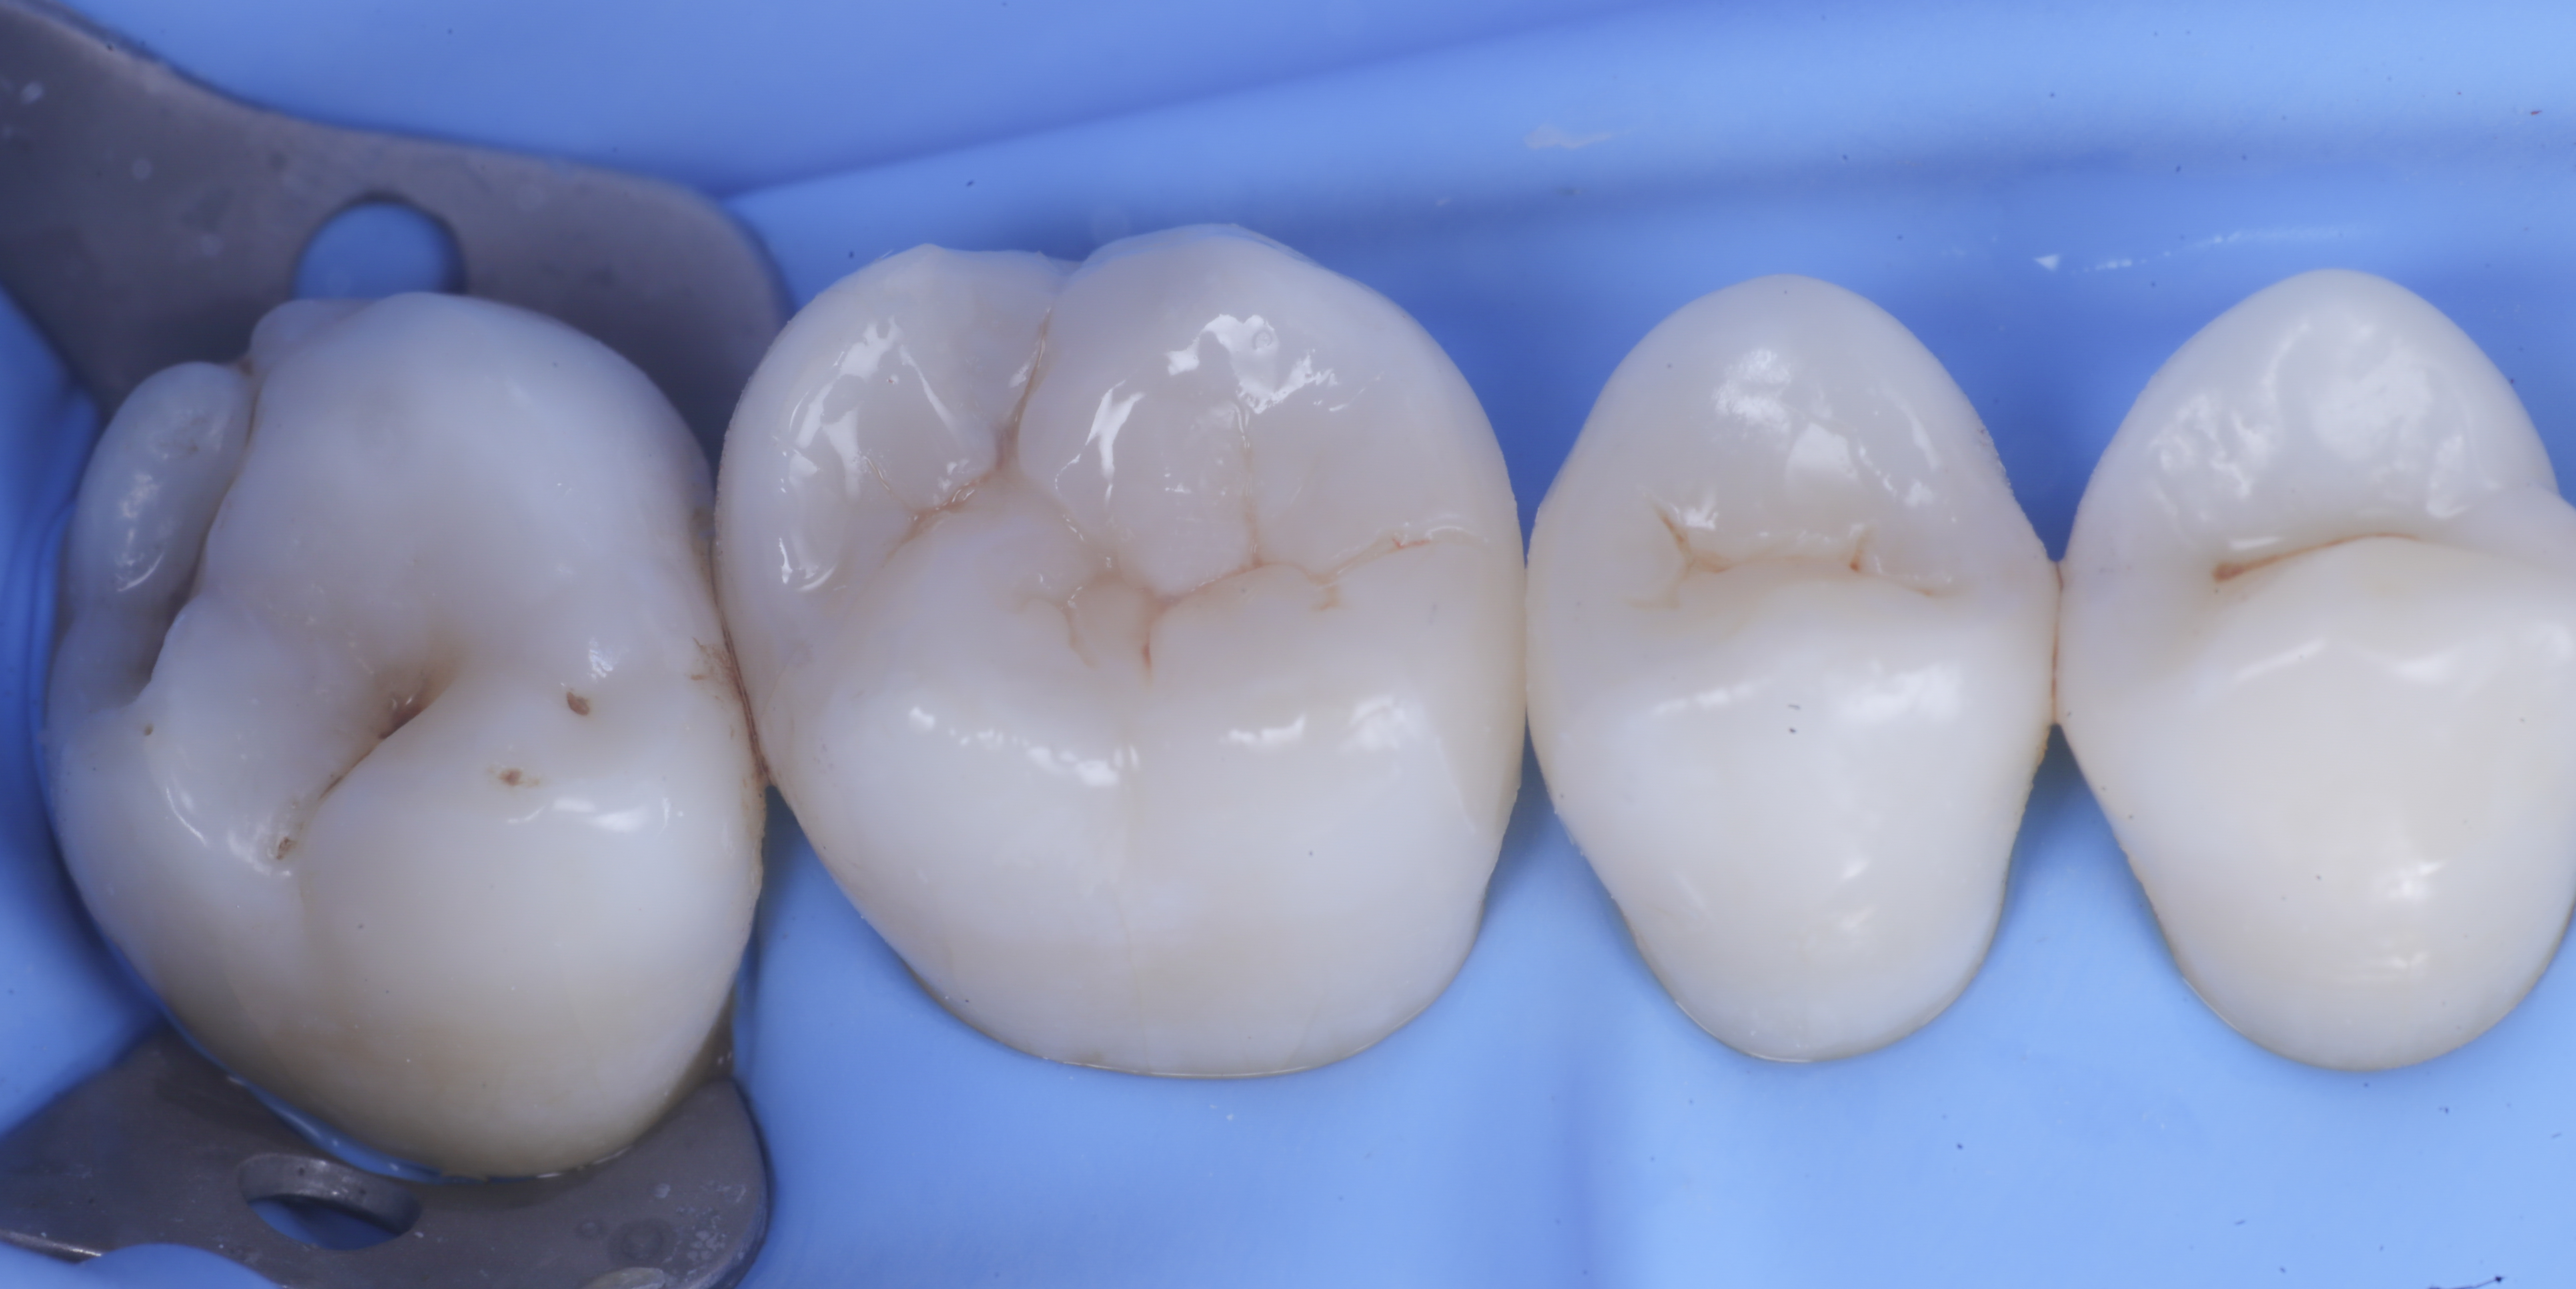

foto 1 Fotografia iniziale

foto 8 Modellazione ed aspetto occlusale